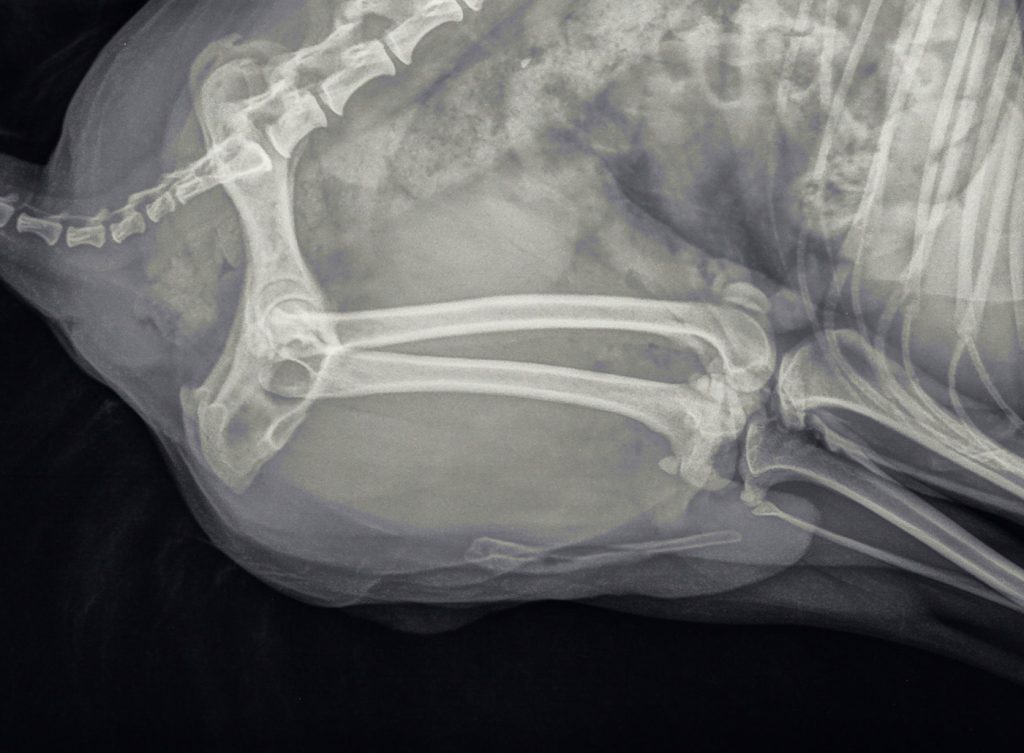

De röntgenfoto

Uit de röntgenfoto bleek inderdaad dat er meerdere steentjes in de plasbuis aanwezig waren, die een vrije uitstroom van urine belemmerden. Tevens waren er verschillende steentjes in de blaas zichtbaar. De enige oplossing voor dit probleem was om operatief de blaas te openen, de steentjes daaruit te verwijderen en vervolgens via een katheter proberen de steentjes uit de plasbuis terug te spoelen naar de blaas. Als dit niet zou lukken, zou er een opening in de plasbuis gemaakt moeten worden, wat dan als plasopening zou gaan fungeren.